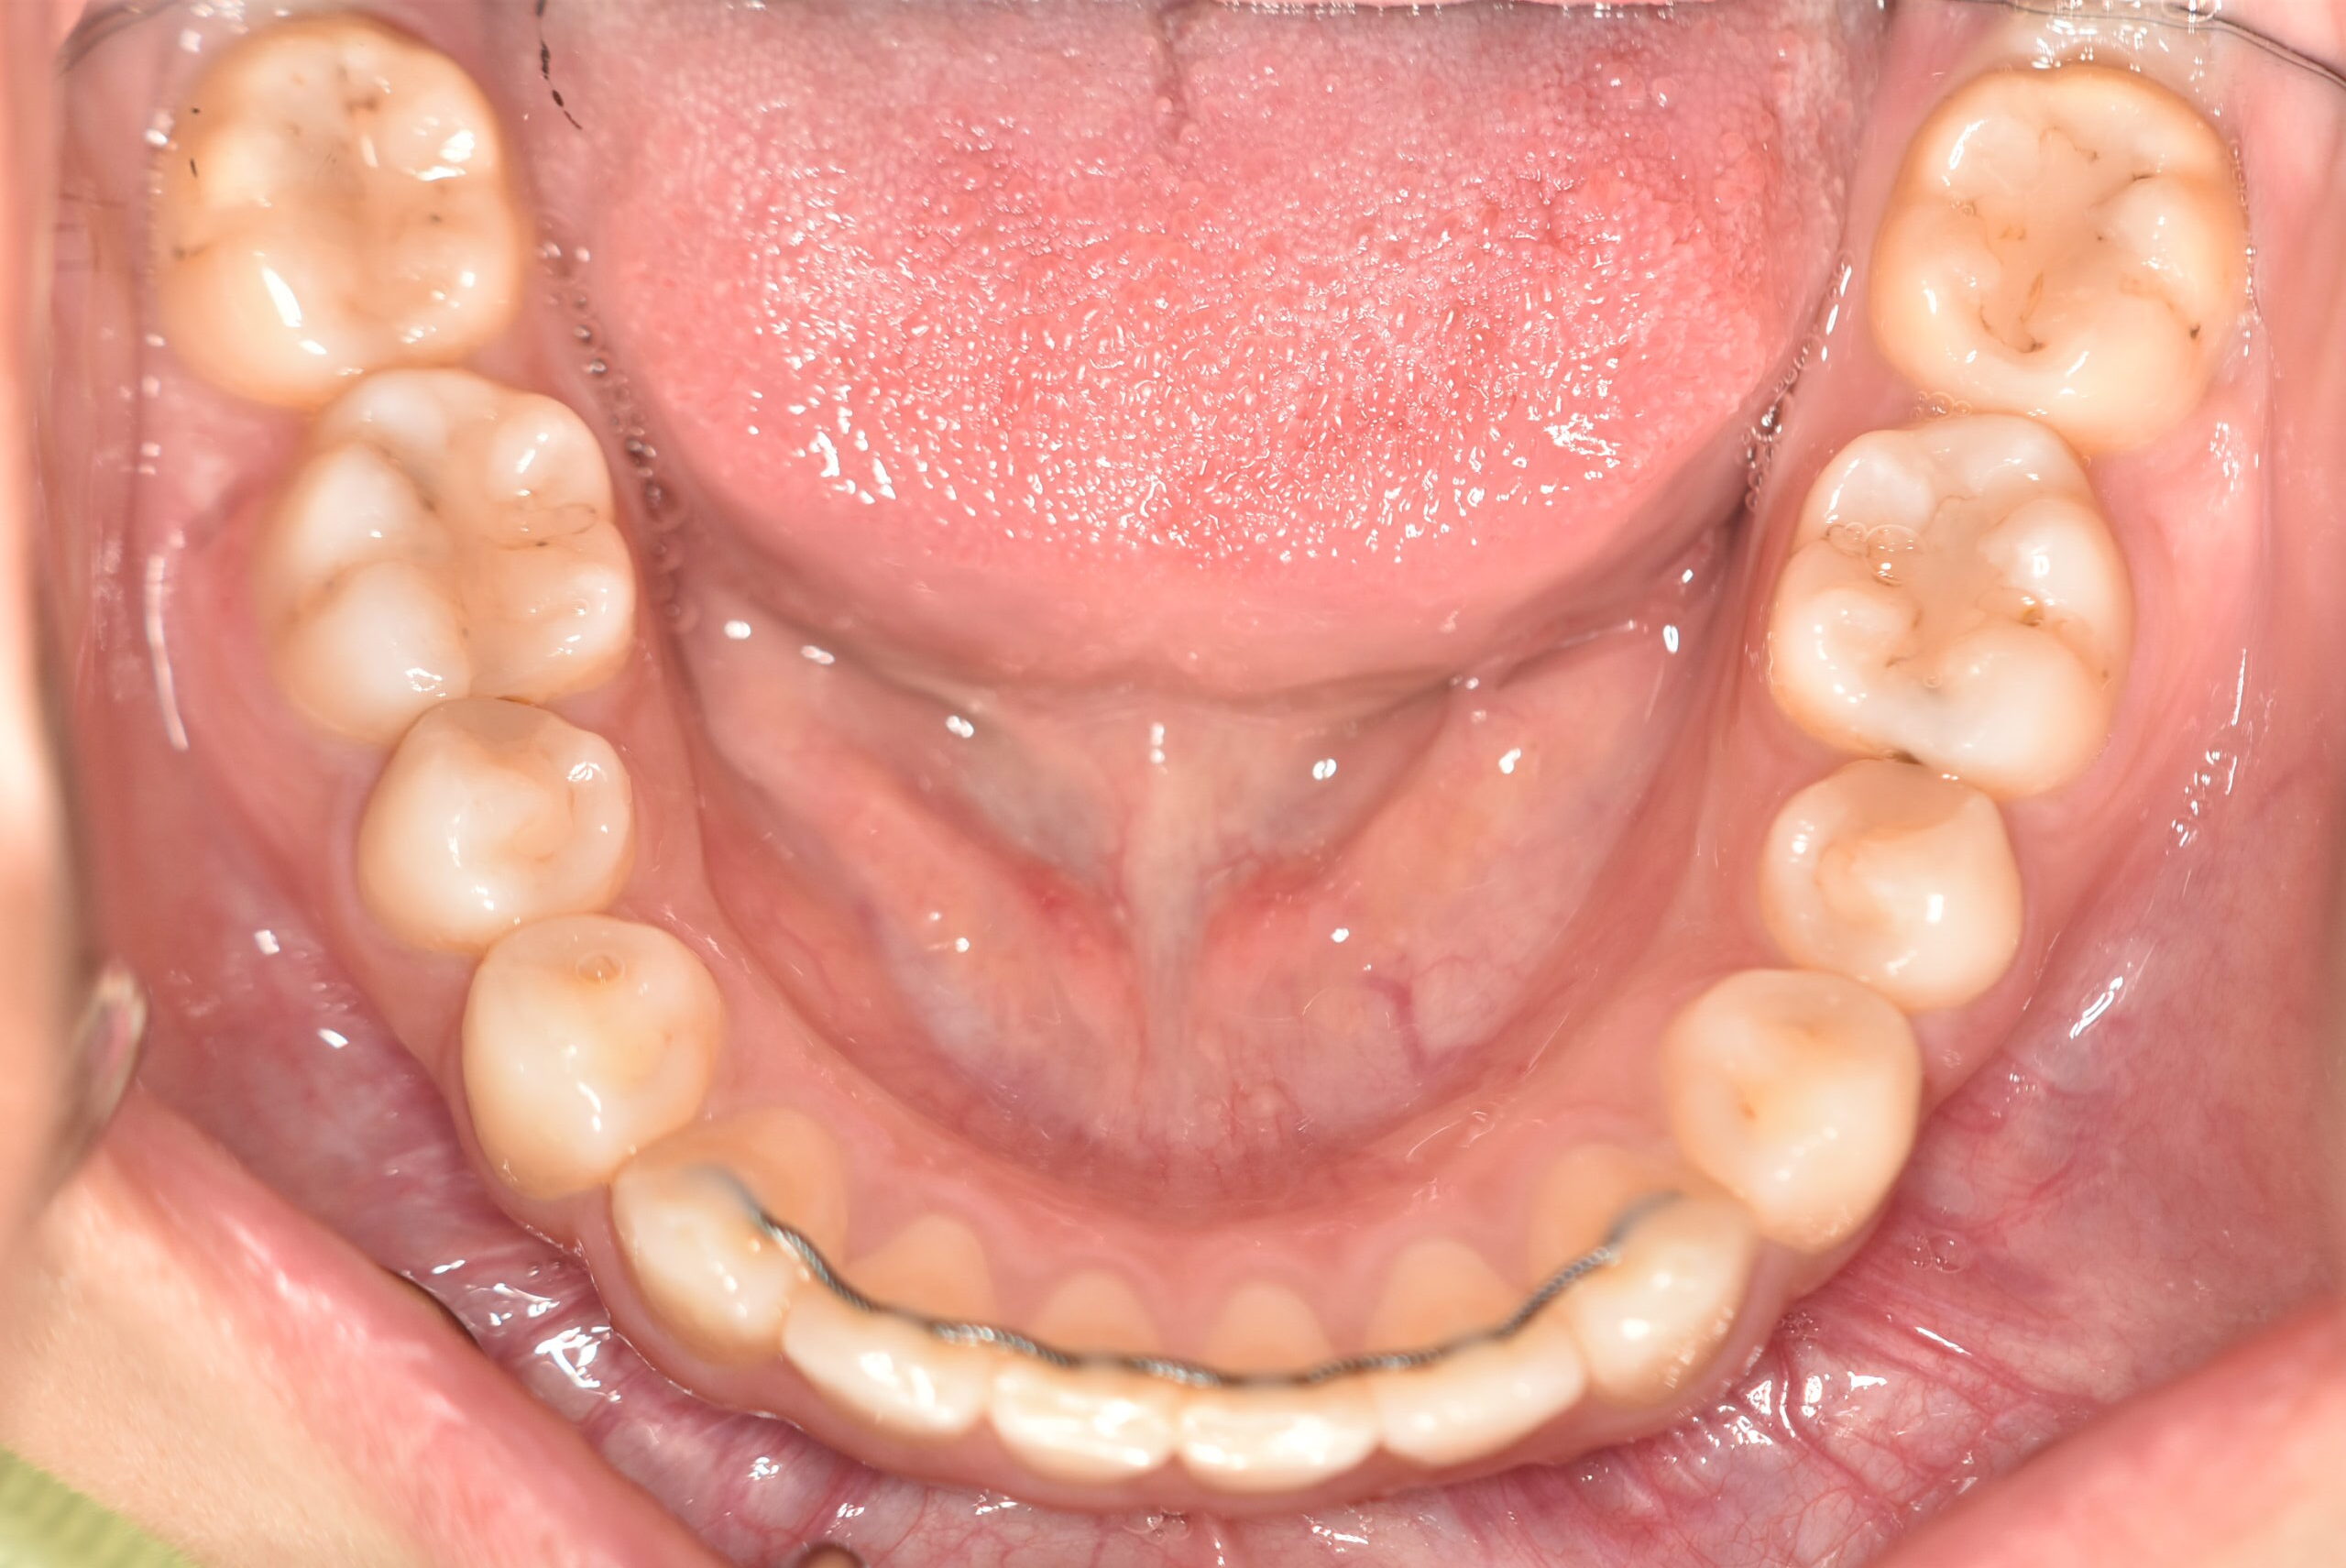

| 治療内容の詳細 | 初診時19歳の女性で、歯のがたつき、かみ合わせを気にされ来院されました。 検査の結果、上顎前歯部叢生を伴うアングルⅡ級1類不正咬合と診断しました。 治療としては、非抜歯の上、セルフライゲーション装置(デーモンシステム)で配列を行いました。 同時に顎間ゴムにて咬合関係の改善を行いました。 治療期間は、2年2ヶ月でした。 |